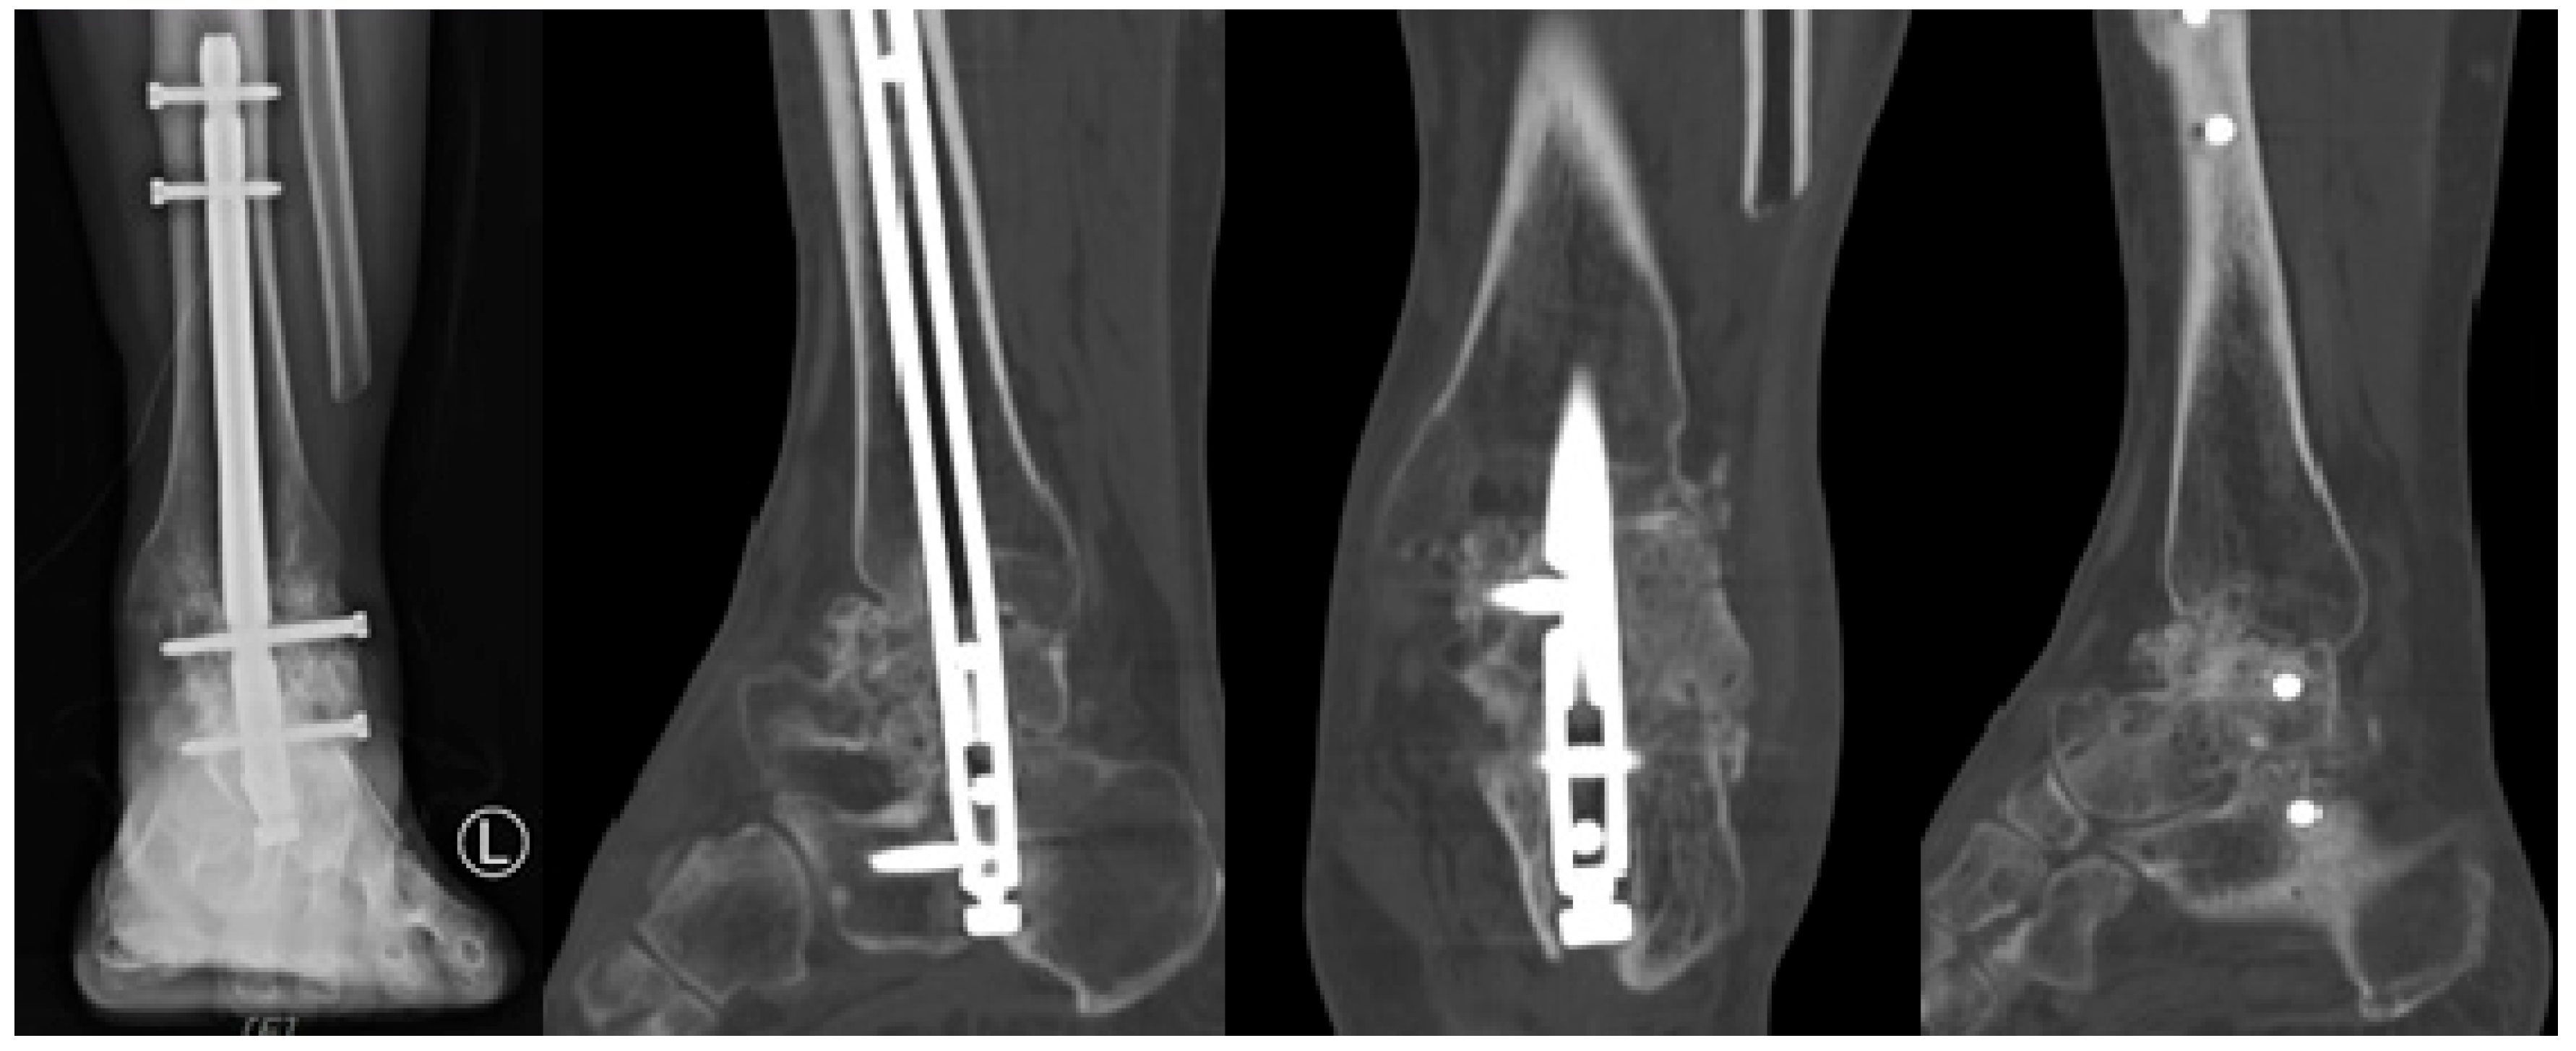

Autologous bone grafts were also utilized intraoperatively. The excised fibular shaft and resected talar fragments were morselized using a bone mill and used as local cancellous graft material to fill any residual defects and augment the fusion site (Figure 4). The shaped allograft was inserted into the prepared talar void and temporarily stabilized with multiple Kirschner wires (Figure 5). Final fixation was achieved with a retrograde intramedullary (IM) nail system (Stryker® T2 Ankle Arthrodesis Nail), inserted from the plantar surface of the calcaneus through the talus into the tibia. Additional fixation with two 3.5 mm cannulated screws targeting the residual talar head or anterior portion of the graft was applied in cases where enhanced rotational or axial stability was deemed necessary (Figure 6).

Figure 6. Postoperative radiograph demonstrating fixation of the talar allograft to the residual talar head using two 3.5 mm cannulated screws for structural stability.

2.3. Postoperative Care

Postoperatively, patients were immobilized in a non-weight-bearing cast for 4 weeks to ensure initial stabilization and healing. Following this initial immobilization period, patients were transitioned to wearing controlled ankle motion boots for an additional 4 weeks to maintain non-weight-bearing status. After the total 8-week period of non-weight-bearing, patients began progressive, tolerable weight-bearing activities. Full weight-bearing was permitted at 12–16 weeks post-surgery, depending on individual patient progress and radiographic evidence of graft incorporation and arthrodesis (Figure 7 and Figure 8).